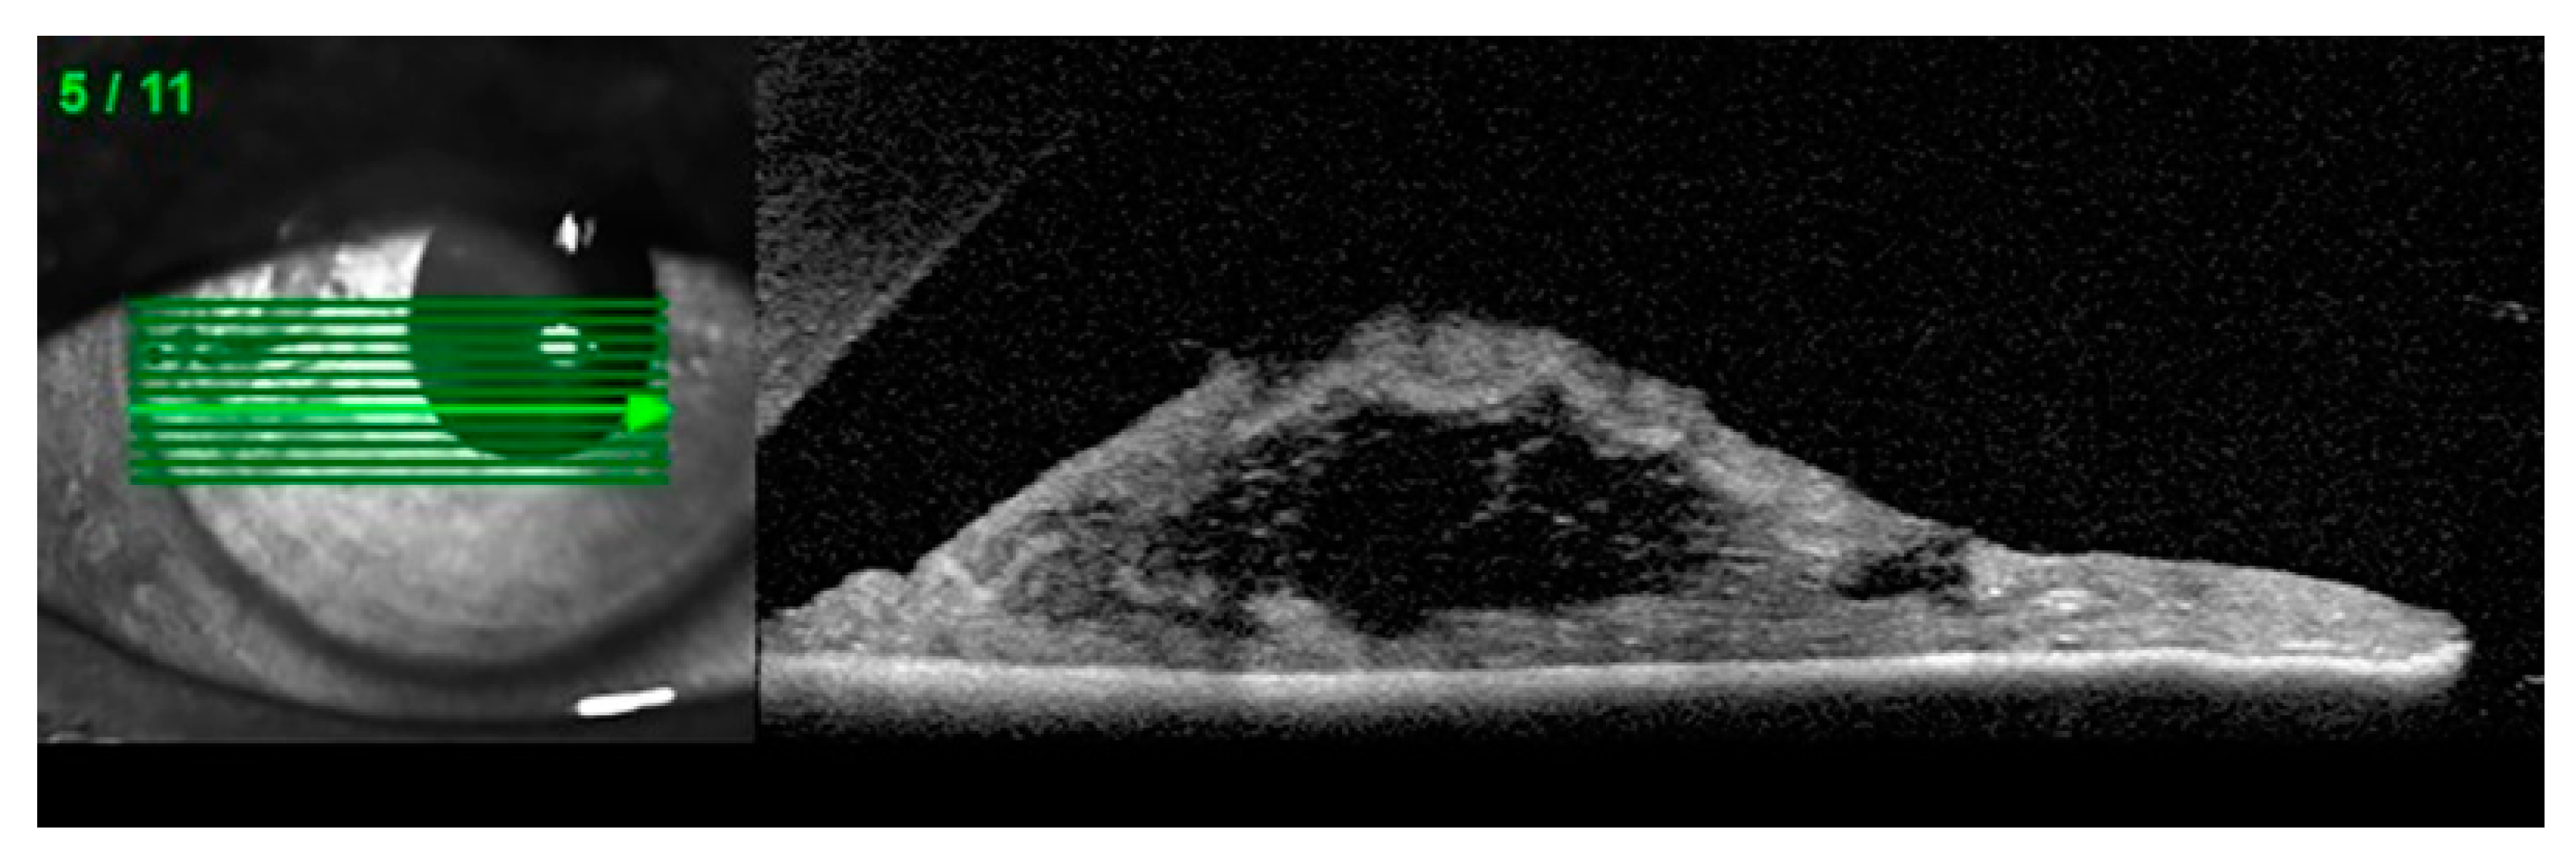

Anterior segment optical coherence tomography (AS-OCT), ultrasound biomicroscopy (UBM) and Scheimpflug imaging are complementary diagnostic options in patients with suspected iridoschisis. (Figure 3) [10,27,28]

Figure 3. Anterior segment optical coherence tomography (AS-OCT): Disorganization of the iris stroma corresponding to iridoschisis (own source).